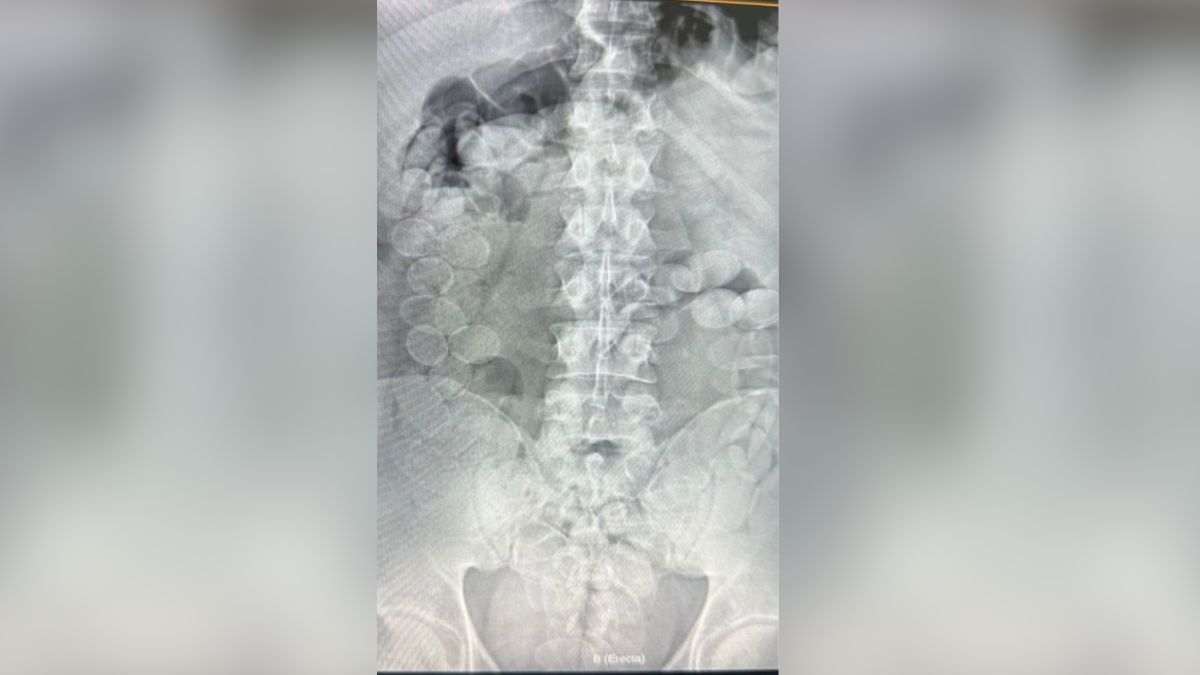

Según le confirmó el fiscal federal Gustavo Onel a AIRE, todo comenzó cuando durante un control de documentación sobre el ómnibus, un perro detector de la GNA marcó que había estupefacientes . Tras la requisa de los bolsos, que dio negativa, el perro continuó marcando en dirección a los detenidos.

Las dos personas mostraron signos de descompostura, por lo que fueron trasladados a un